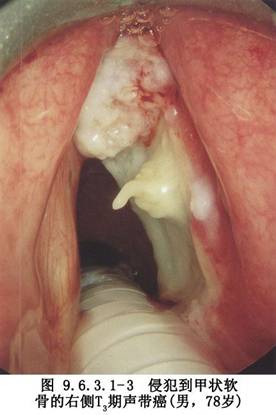

2.聲門癌 ①選擇性T3;②T4;③侵犯杓間區;④侵犯甲狀軟骨或環狀軟骨;⑤向聲門下擴展(圖9.6.3.1-2,9.6.3.1-3)。